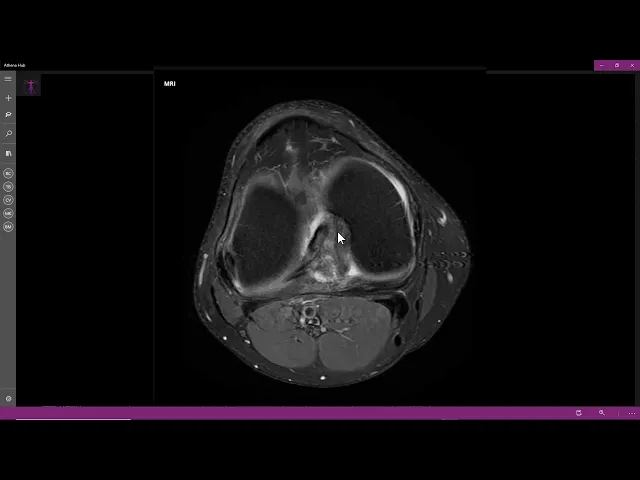

olá saudações a todos meu nome é israel são médico radiologista e patologista e neste vídeo para estudantes e profissionais da área de saúde vamos conversar sobre este exame temos aqui uma ressonância magnética do joelho direito cortes no plano axial sequência ponderada em t2 com saturação de gordura aqui na porção inferior temos tíbia fíbula e já vemos aqui um músculo poplíteo apresenta hipersinal com essas estriações aqui no seu ventre muscular bom então uma lesão grau dois uma distensão muscular lesão grau dois aí no músculo poplíteo aqui do tendão do músculo poplíteo vamos acompanhar o tendão está

normal está inserindo normalmente ele a lesão muscular no poplíteo na lesão grau 21 o e observe o ligamento cruzado anterior aqui está normal agora olha o posterior o posterior normalmente a gente vê uma bola preta que ele já tem hipersinal bastante alterado veja hipersinal nele aqui ainda está preservado e aqui a gente perde ele parece que tem uma ponta aqui e a outra parte dele é que então suspeita-se de uma ruptura completa do cruzado posterior e o cruzado anterior tá aqui normal e aqui no coronal a gente vê nitidamente a lesão do músculo poplíteo é

que está o músculo público com esses traços as estrias de hipersinal que é são áreas de solução de continuidade na de ruptura de fibras com edema da josete e o tendão dele tá normal como a gente já viu tá aqui o ligamento colateral lateral um pouco espessado ligamento colateral medial normal ele se paciente tem um ministro discóide completo lateral aqui minas discóide vejo medial aqui como é que é e o lateral vem até o centro da articulação ligamento cruzado anterior tá normal nasci aqui vem para cá e o ligamento cruzado posterior realmente rompeu aqui está

rotura do ligamento cruzado posterior veja aí completamente roto aqui tá uma parte dele a rotura ea outra parte dele é sim ser indo ali todo espessado com hipersinal a gente vem vem essa bolota aqui vem de repente a rotura tão não há dúvida rotura completa do cruzado posterior estiramento lesão grau dois do músculo poplíteo e uma lesão graundo colateral lateral com pequeno hipersinal aqui e no sagital vamos identificar aí ela esse anormal e o lcp tá aqui a gente ver ele todo borrado e aqui é a área da ruptura altura dele aqui veja que a

rotura ficou melhor de ver no coronal na e observe que no coronal a gente viu a ruptura bem melhor de qualquer forma ruptura do lcp cruzado posterior e aqui o ministro discóide lateral o ok nesse vídeo objetivo era mostrar aí nem imagem típica de ruptura do lcp que não é muito frequente no dia a dia obrigado e até o próximo vídeo